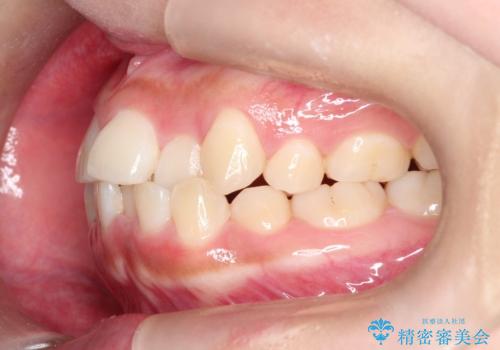

- 前歯のでこぼこが気になると来院されました。

奥歯の噛み合わせは綺麗に噛んでいたため、前歯の叢生(でこぼこ)を、短期間で治療完了するように計画しました。